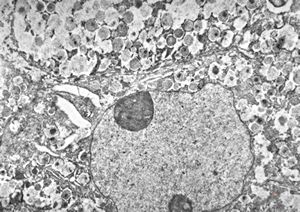

M,41y. | hairy cell leukemia - spleen - ribosome-lamella complex in tricholeukocyte